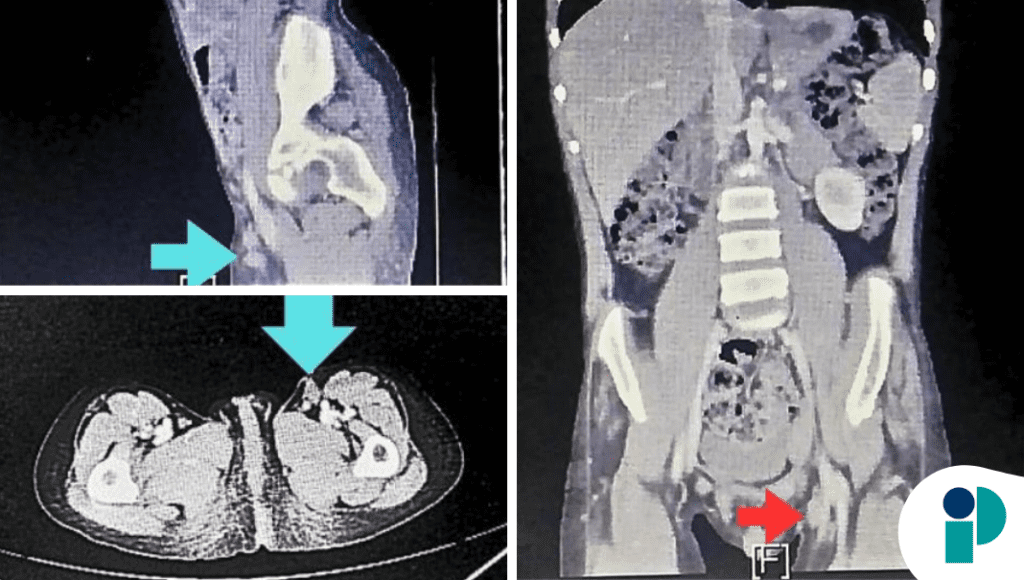

El paciente consultó por dolor abdominal progresivo, distensión y síntomas compatibles con obstrucción intestinal, lo que motivó la realización de estudios de imagen. Estos evidenciaron invaginación intestinal (intususcepción), un hallazgo infrecuente en adultos y que, a diferencia de los niños, suele estar asociado a una causa estructural subyacente.

Ante este escenario, se decidió manejo quirúrgico. Durante la intervención se identificó una masa localizada en el intestino delgado (íleon), responsable del fenómeno obstructivo. La lesión actuaba como punto de tracción, favoreciendo que un segmento intestinal se introdujera dentro de otro.